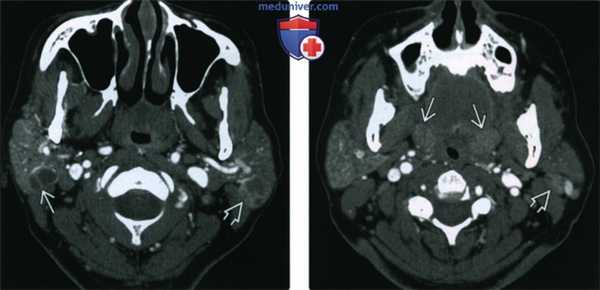

(Слева) КТ с КУ, аксиальная проекция у пациента с объемным образованием шеи слева. Плотность обеих околоушных желез увеличена, в правой железе определяется многокамерная киста, в левой - смешанное кистозно-солидное образование.

(Справа) КТ с КУ, аксиальная проекция, этот же пациент. Определяется единичный увеличенный околоушной узел слева и гипертрофия небных миндалин. По результатам КТ пациенту было рекомендовано обследование на ВИЧ, результат оказался положительным.

(Слева) На аксиальной КТ с КУ визуализируются множественные мелкие контрастирующиеся очаги с диффузным поражением обеих околоушных желез, характерные для персистирующей генерализованной паротидной лимфаденопатии. Данные очаги представляют собой увеличенные лимфоузлы.

(Справа) На корональной реформатированной КТ с КУ у пациента с ВИЧ определяются очаги в обеих околоушных железах, образованные кистозным и солидным компонентами, сопоставимые с ДЛЭП при ВИЧ.